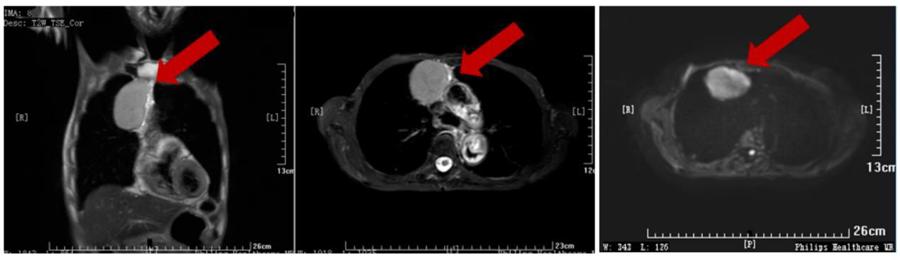

胸部MRI,纵隔肿瘤无增强可以清楚显示病灶与血管分界。

胸部MRI,MRI对于最常见的肺结节显示能力以及对于肺内小结节的检出率已经大幅度提高。而且MRI比CT更容易鉴别肿块性质。